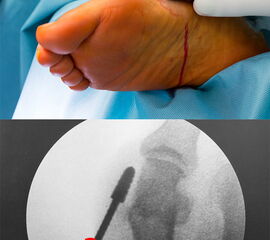

Ein vollständiges Umdenken und Umlernen ist erforderlich für den Chirurgen, der in der offenen OP-Technik mit dem Leitspruch groß geworden ist: „Nie schneiden, wo man nichts sieht!“, da die intraoperative Kontrolle des eigenen Tuns in der MIS ausschließlich über Durchleuchtung mit dem C-Bogen erfolgen kann.

• Sämtliche Osteotomien werden in der sogenannten „Safe-Hole-Technik“ durchgeführt: Perforieren der ersten Kortikalis mit der Fräse, so dass der schneidende Anteil der Fräse intramedullär zu liegen kommt. Nun kann die Osteotomie aus dem Markraum heraus komplettiert werden ohne Gefahr einer akzidentellen Verletzung umliegender Strukturen.